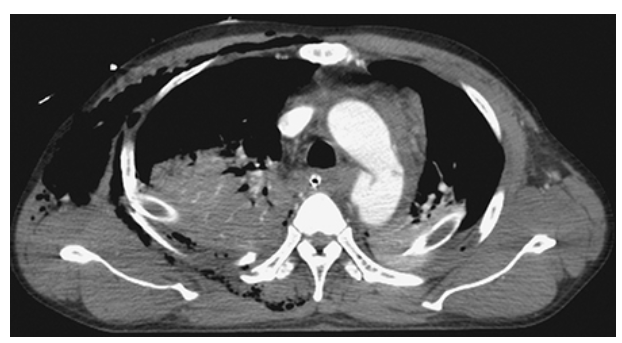

Type A Dissecting Aneurysm. Axial CT with IV contrast demonstrates a Type A aortic dissecting aneurysm involving both the ascending and descending thoracic aorta showing a double lumen separated by the intimal flap.